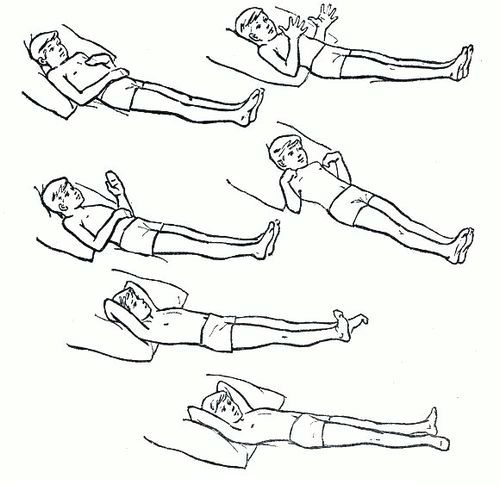

Після купірування симптомів запалення основне завдання лікування - запобігання ускладнень з боку суглобів (хронічного запалення, тугорухливості, зрощень суглобів (анкилозов) і ін.). Для досягнення цієї мети хворий починає робити ЛФК: вже в ліжку рухає кінцівками, розробляючи уражений суглоб і повертаючи йому повний обсяг рухів. У міру поліпшення стану обсяг вправ і їх інтенсивність збільшують.

Простий комплекс ЛФК при постільному режимі